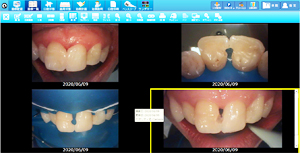

• ラバーダムを使用した治療画像